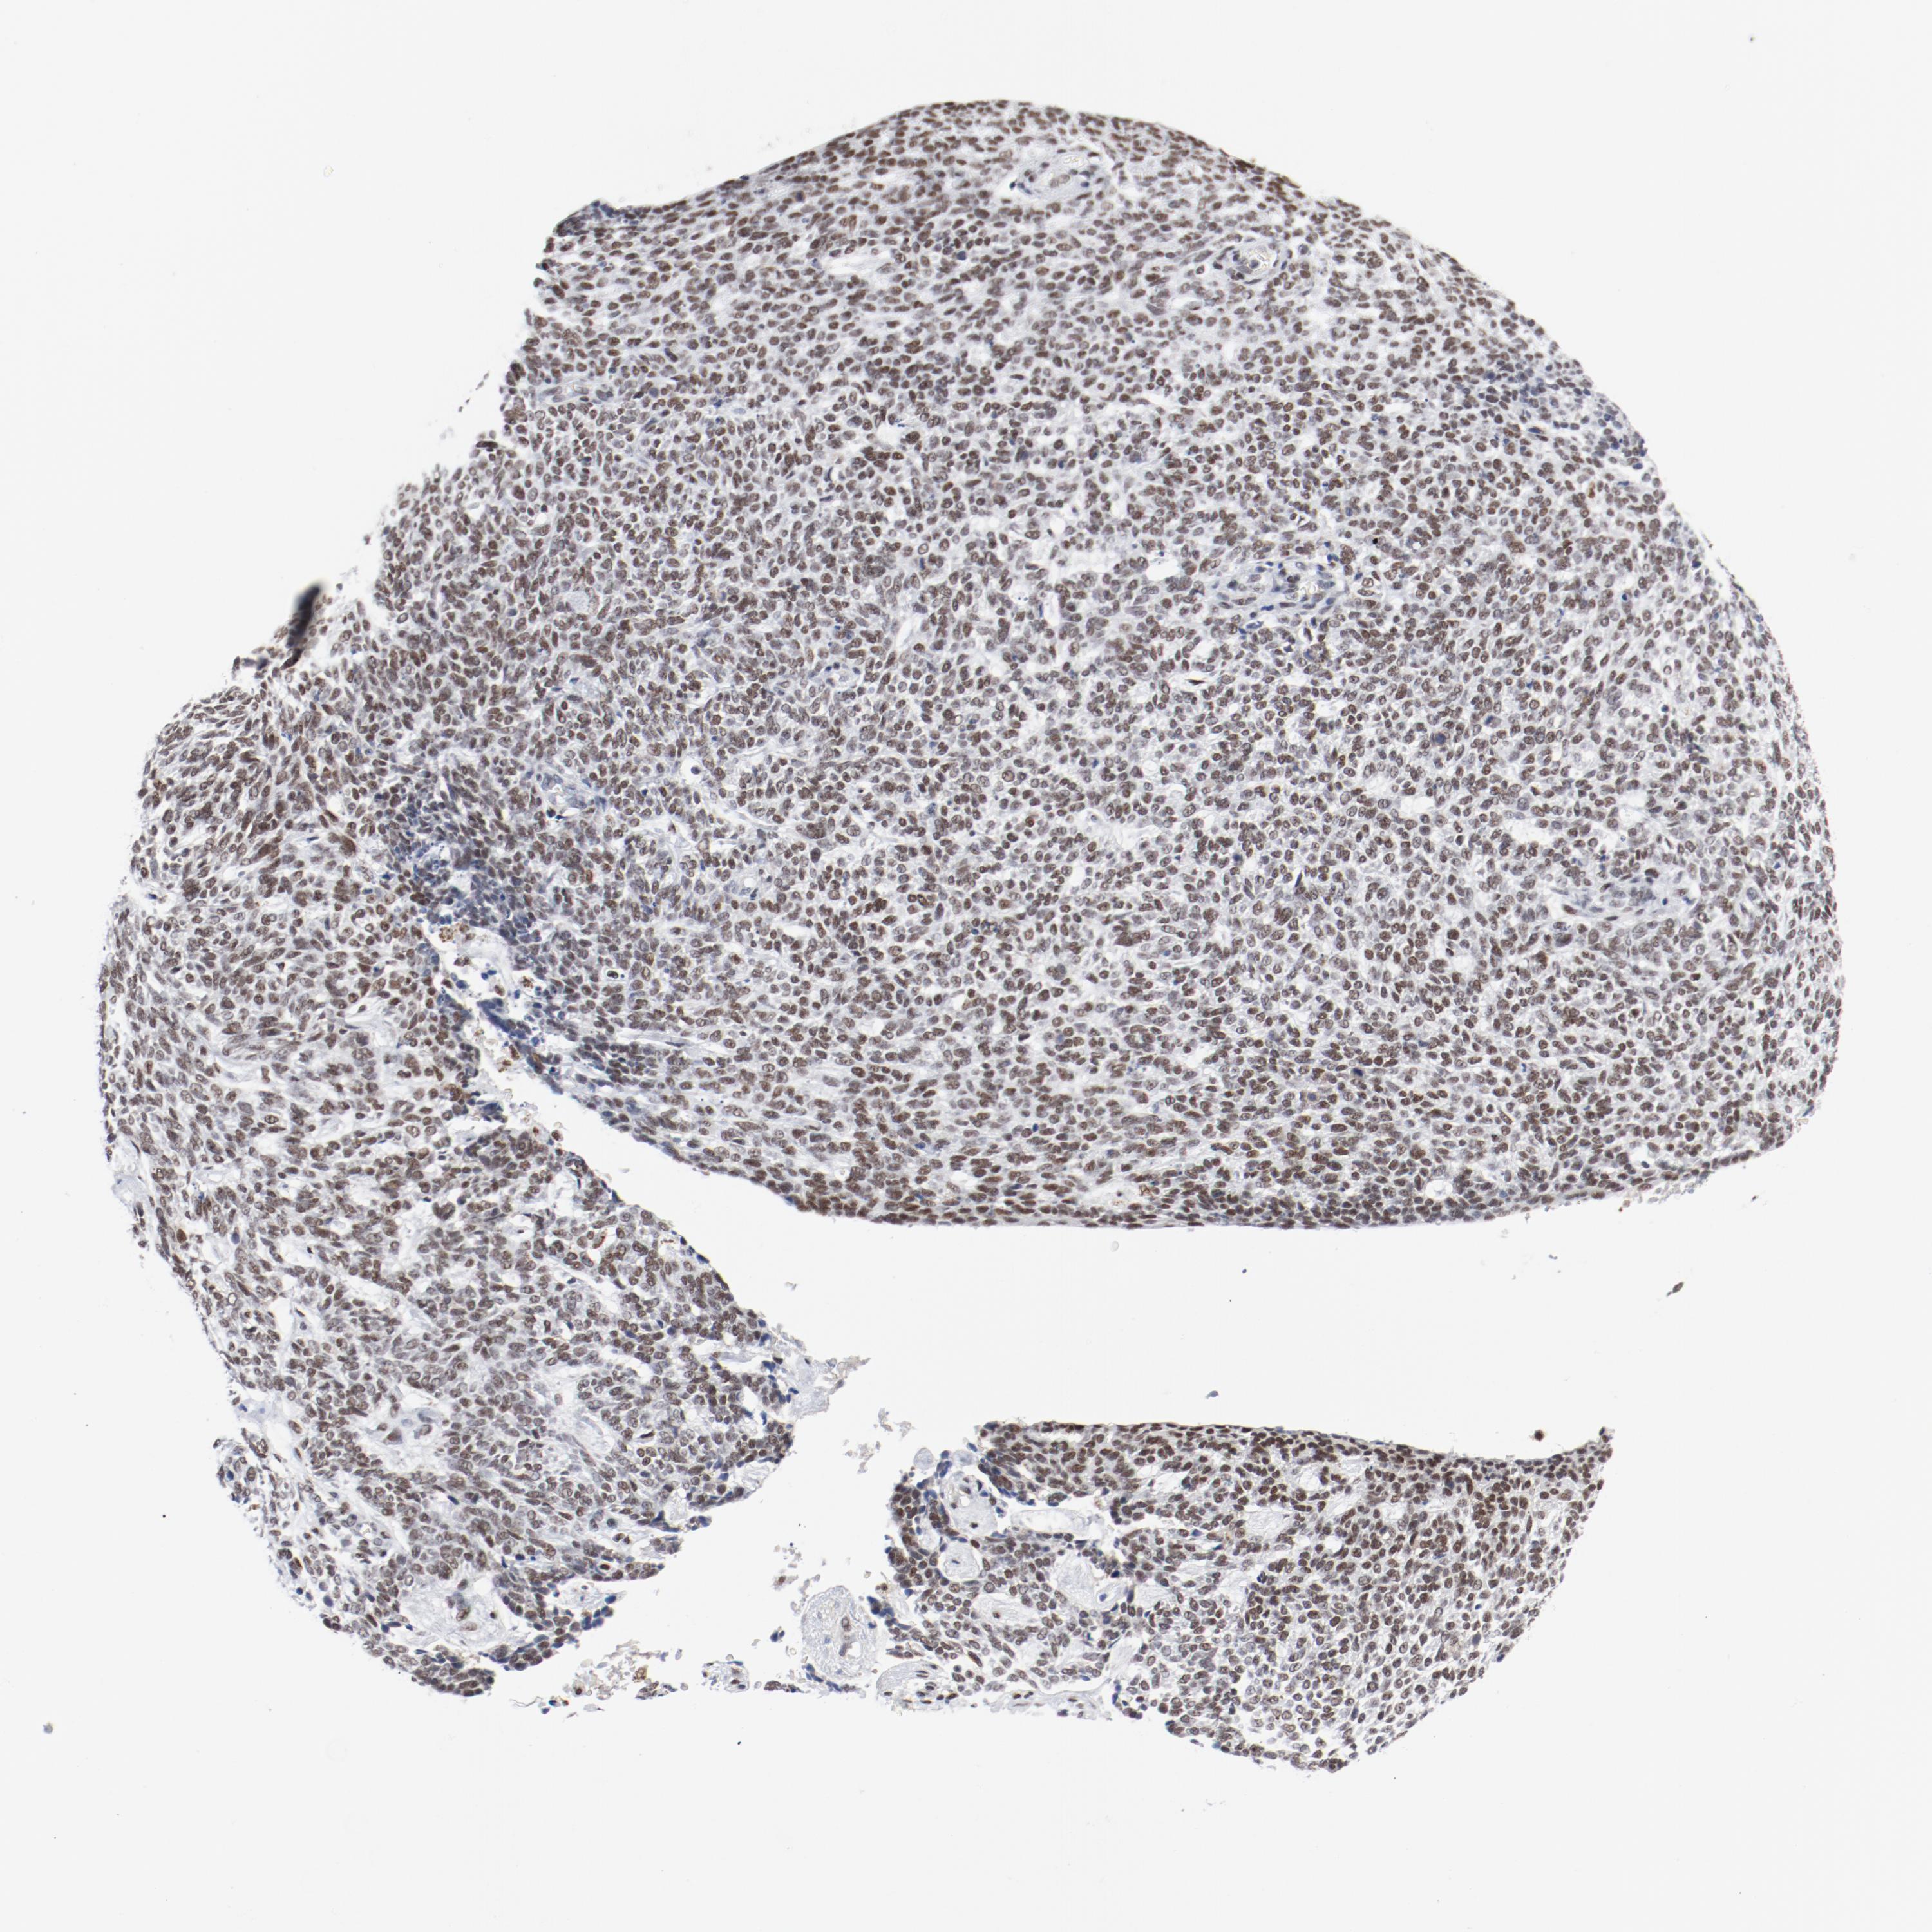

SKIN CANCER - Protein expressioni

A mouse-over function shows sample information and annotation data. Click on an image to view it in a full screen mode. Samples can be filtered based on level of antibody staining by selecting one or several of the following categories: high, medium, low and not detected. The assay and annotation is described here.

Antibody stainingi

Antibody staining in the annotated cell types in the current human tissue is reported as not detected, low, medium, or high, based on conventional immunohistochemistry profiling in selected tissues. This score is based on the combination of the staining intensity and fraction of stained cells.

Each image is clickable and will lead to virtual microscopy that enables deeper exploration of all samples and also displays staining intensity scores, fraction scores and subcellular localization as well as patient and tissue information for each sample.

Antibody CAB004318

Squamous cell carcinoma, NOS

Basal cell carcinoma